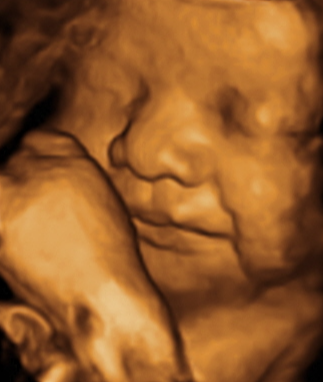

역아 였을 때 24주와 30주 입체 초음파 사진을 보면 얼굴옆에 다리가 있고 다리를 안고 있는 것 처럼 보였고 얼굴은 오른쪽 얼굴을 보였었는데

정상 자세로 돌아온 후엔 얼굴도 평온해 보이고 ㅋㅋ 더 이상 얼굴 옆에 다리가 보이지 않고 왼쪽 얼굴이 보였어요!